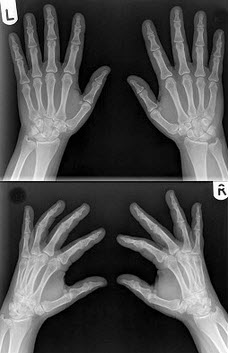

186、单项选择题

男,根据其正常手的影像图像,判断其最可能的年龄()

A.16岁左右

B.26岁左右

C.36岁左右

D.76岁左右

E.56岁左右